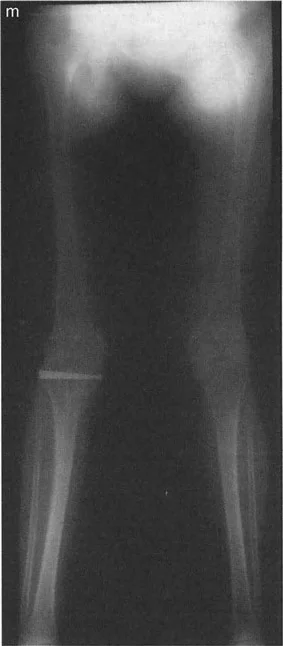

في دراسة شاملة لإعادة محاذاة الطرف السفلي، يركز العديد من الأطباء على الانحرافات في عظام الفخذ والساق، والتي تؤثر على المحور الميكانيكي العام للساق. يتم حساب زوايا معينة لتحديد مركز دوران الانحراف (CORA) بدقة. ومع ذلك، هناك مكون حاسم وغالباً ما يُساء فهمه في محاذاة الطرف السفلي يكمن مباشرة داخل المفصل نفسه: تشوه خط مفصل الركبة.

إن المصادر المتبقية لاختلال المحاذاة تنبع من فقدان العظام والغضاريف، أو خلل التنسج الخلقي والتنموي لأسطح مفصل الركبة. السبب الأكثر شيوعاً لدى البالغين هو فقدان الغضاريف غير المتماثل من الجزء الإنسي أو الوحشي للركبة، وهو أمر نموذجي في حالات التهاب المفاصل المتقدم أو التنكس ما بعد الصدمة. أما لدى الأطفال، فتسيطر حالات مثل مرض بلونت أو توقف نمو صفيحة النمو.

- مرض بلونت (تقوس الساق): في مرض بلونت الشديد لدى الرضع أو المراهقين، تتميز الحالة بانخفاض شديد وميل إنسي للهضبة الظنبوبية الإنسية. إذا رسمت الخطين، فإن خطي الهضبة الإنسية والوحشية يكونان بزاوية حادة بالنسبة لبعضهما البعض، ويتقاطعان بالقرب من مركز الركبة. وهذا يخلق دفعاً تقوسياً شديداً أثناء المشي.

- متلازمة إليس-فان كريفيلد (خلل التنسج الغضروفي الجلدي): تؤدي هذه الحالة الوراثية إلى انخفاض "متدرج" مميز في الهضبة الظنبوبية الوحشية. ومن المثير للاهتمام أن خطي الهضبة غالباً ما يظلان متوازيين لبعضهما البعض، لكنهما يقعان على مستويات أفقية مختلفة تماماً، مما يخلق فرقاً كبيراً في المستوى وتشوهًا شديدًا في وضعية الركبة (valgus).